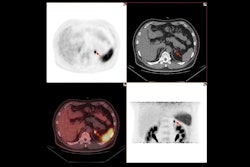

Gallium-68 (Ga-68) pentixafor binds to the CXCR4 receptor on inflammatory cells present in atherosclerotic plaques, which makes it possible to find and treat atherosclerosis in its early stages (JNM, March 2017, Vol. 58:3, pp. 499-506).

Ga-68 pentixafor's ability to bind specifically to inflammatory cells in atherosclerotic plaques was validated in animal models and human subjects. Images showed inflammation in plaques in the abdominal aorta and right carotid artery of atherosclerotic rabbits. The researchers also confirmed that the radiotracer detected atherosclerotic plaques located in the carotid arteries of a small number of human patients.